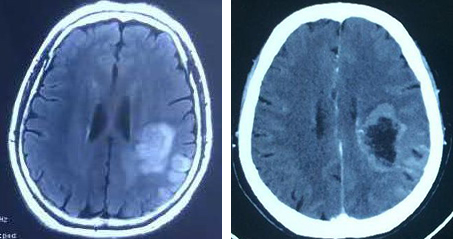

女性患者,67岁,2016年9月经查发现左侧颞顶叶占位性病变,于2016年11月7日于天坛医院行活检病理结果提示胶质母细胞瘤(WHO IV级),家属拒绝放化疗后来我院于2016年11月16日行声动力疗法治疗,入院时患者右侧肢体肌力3级,治疗后3天患者右侧肢体肌力4-级,监测血常规、肝肾功能正常,一月后复查头颅MRI增强提示肿瘤明显消融、坏死、缩小等征象。

2016年10月26日声动力治疗前,2016年12月14日声动力治疗后28天 病例2: 患者女性,6岁,2014年9月发现左侧腹膜后神经母细胞瘤(IV期),化疗1年后行肿瘤大部切除术。2016年7月13日入院时超声提示肿物大小约4.0cm×2.6cm。2016年7月16日注射光敏剂后行声动力治疗,期间患者无不适主诉及异常表现,血常规、肝肾功能指标正常。2016年8月26日超声提示肿物大小约2.5cm×1.5cm×2.2cm。